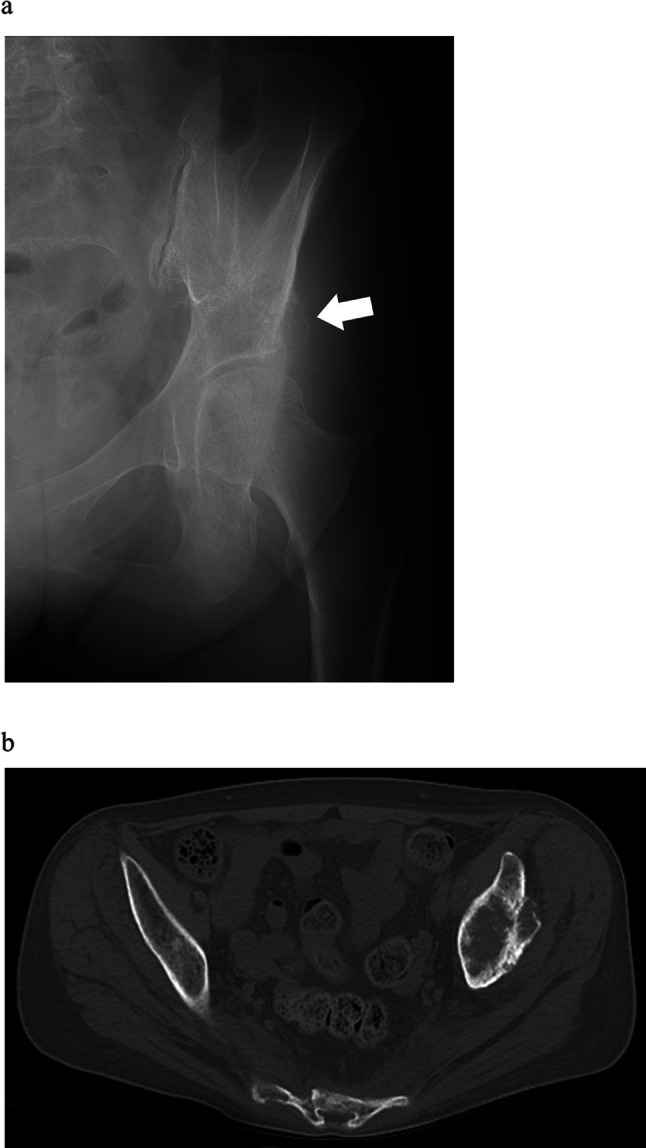

Bone metastasis in the periacetabular region usually causes severe pain and functional disability. Some surgical procedures, such as the Harrington surgery and percutaneous cementoplasty, have been reported as treatment options for periacetabular bone metastases with limited efficacy. The former is highly invasive, while the latter may not allow the injection of a sufficient amount of cement. Here we report two surgical cases using a new modified surgical method (mini-open periacetabular cementoplasty: MO-PAC) consisting of tumor curettage and cementoplasty through a small incision.

髋臼周围骨转移通常引起剧烈疼痛和功能障碍。一些外科手术,如Harrington手术和经皮骨水泥成形术,已被报道为髋臼周围骨转移的治疗选择,但疗效有限。前者是高度侵入性的,而后者可能不允许注入足够数量的水泥。在此,我们报告了两例手术病例,采用了一种新的改良手术方法(迷你开放髋臼周围骨水泥成形术:MO-PAC),包括肿瘤刮除和小切口骨水泥成形术。